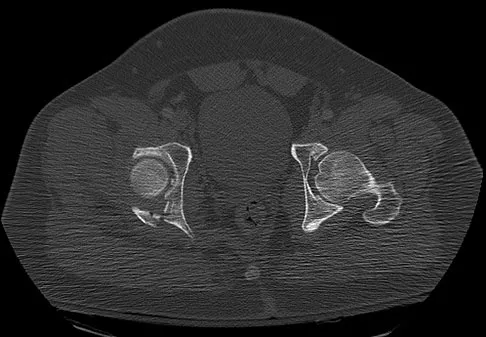

Figures 22a and 22b show the radiographs of a patient who reports stiffness of the hip and associated pain. Management should consist of

Explanation

The patient has grade IV heterotopic ossification with the limb in an abnormal nonfunctional position. Treatment should consist of excision of the bone to restore hip motion and prophylaxis to prevent recurrent formation. The best time to excise the bone is controversial, with no conclusive evidence supporting early or late excision. Pellegrini VD Jr, Koniski AA, Gastel JA, Rubin P, Evarts CM: Prevention of heterotopic ossification with irradiation after total hip arthroplasty: Radiation therapy with a single dose of eight hundred centigray administered to a limited field. J Bone Joint Surg Am 1992;74:186-200.